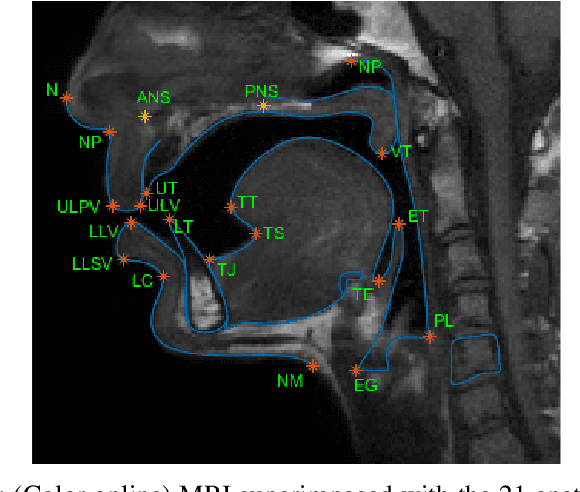

Abstract:The various speech sounds of a language are obtained by varying the shape and position of the articulators surrounding the vocal tract. Analyzing their variability is crucial for understanding speech production, diagnosing speech and swallowing disorders and building intuitive applications for rehabilitation. Magnetic Resonance Imaging (MRI) is currently the most harmless powerful imaging modality used for this purpose. Identifying key anatomical landmarks on it is a pre-requisite for further analyses. This is a challenging task considering the high inter- and intra-speaker variability and the mutual interaction between the articulators. This study intends to solve this issue automatically for the first time. For this purpose, midsagittal anatomical MRI for 9 speakers sustaining 62 articulations and annotated with the location of 21 key anatomical landmarks are considered. Four state-of-the-art methods, including deep learning methods, are adapted from the literature for facial landmark localization and human pose estimation and evaluated. Furthermore, an approach based on the description of each landmark location as a heat-map image stored in a channel of a single multi-channel image embedding all landmarks is proposed. The generation of such a multi-channel image from an input MRI image is tested through two deep learning networks, one taken from the literature and one designed on purpose in this study, the flat-net. Results show that the flat-net approach outperforms the other methods, leading to an overall Root Mean Square Error of 3.4~pixels/0.34~cm obtained in a leave-one-out procedure over the speakers. All of the codes are publicly available on GitHub.